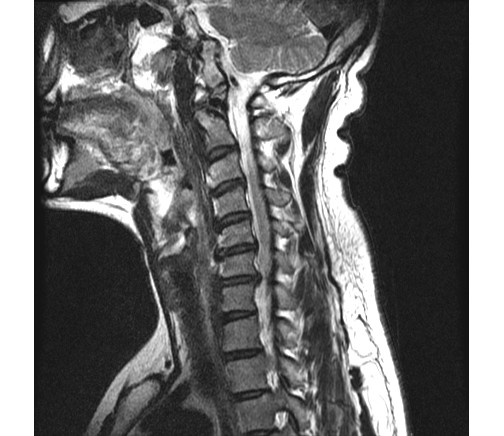

2013 2 ʴٸ 鼭 ѵ ӵǾ ȼ ִ 湮Ͽ а˻(MRI) ް, 㸮ũ Ű ִٴ ô ڼ, Ű漺ü ް ũ ٰ ĥ ڰ ʰ ̿ ణ ְ, ȿ Ÿ ĥ ȣ ٽ ġḦ Ҵ **** 湮Ͽ x-̿,MRIԿ غ ʿ Ʒ(4.5.6.7) 3 ũ Ƣ Ű ִٴ ¿ϴ. ſ Ͽ ٰ մϴ. ϴ Űֻ ġ Ÿ ¿, Ϻ ߷° ġḦ ̾ϴ. ġ Ŀ ° ȭǸ ñδ ھƼ ߺκ ִ ƾ ȴٰ ߽ϴ. ũ 500 ,ġ 2,500 ȴٰ ߽ϴ. üϿ콺 縦 ϴ 忡 Ŀ üϿ콺 ãƾ ߰ ϴ ϸ鼭 ͳݿ ڷḦ ã ߿ ڸǥغ ˰Եǰ Ͼ ʴ ʱ۵ 鼭 ʱ۵ ܼ ȸ Ͽ ڸǥغ ߽ϴ. ߰ ȸ ȭ ʰ Ͽ غ ξ ϰ پϴ. ڰ ʹ Ͼ ٽ þ ִ ȸ ȣ ȴ Ͽε ұϰ ݹ ȭ Խϴ. ̰ ð ϰ ʰ Ȱ ɴ ڼ ϴ. ϴ ÿ پ ϴ. ͳݿ ** ˷ֽôµ ϰ ƮĪ ̾ϴ. ȸ ó Ȯϰ ϴ Դϴ. ȭȭ ˷ֽôµ Ȯϰ ִ ͵ ű߽ϴ. ǻ ֽð ı ̶ ϴ ϸ鼭 ߰ 30ʾ ϶ ߽ϴ. ῡ ٽϰ ƮĪ ȿ ϰ ٲ۴ٰ ϼ̽ϴ. 鿡 ϴٰ ְų ִ پ ̶ ϸ ȭֽŴٰ ߽ϴ. ̰ͱ ħ ̾ϴ. ῡ Ϸ ϰ ῡ ȸԲ ڷ 帰 Դϴ. ȸԲ ˷ֽ ϸ鼭 ƴ غ ° Ǵ ȭ Դϴ. õ Կ ſ 鿡 ϴ ֽ ڼ Ϸ ϴ, ణ Ÿ° ʹٰ ߽ϴ. ʰ ,Ŀ ƿͼ õ κ(12).Ӹ(8) غ Բ , ȵ ణϰ Ÿ., ⺻ Ӹе 9 غ 30 ǻϴ. Ӹκ 9е ؼ ϰ ֽϴ. ߽ϴ. ȭ ּ̽ϴ. ǻͿ ɾƼ mriϰ Ͽ 帮 Ű澲ٰ ٽ ͽϴ. ȸԲ ʰ ǻ ϴ¹ ˷ֽʴϴ. ǻ տ Ȳ ʰ ɴ ڼ ٲٴϱ ϴ. űԿ ڼ ߿ ƮĪ ü ߿伺 ű ȵ ߽ϴ. ʰ ȸϴ е ʱ۵ ó Ե Ͼ ̷ο Բ ʾƵ ǰڴٴ 밨 ϴ. mri ½ϴ. ȸԲ Ȯϰ Ǵϰ ٽ ȮҶ Ʒ mri øŴϴ. ø Ȯֽð Ź帳ϴ. ---------------------------------------- -- û Ȯϱ Ͽ mri øϴ. |